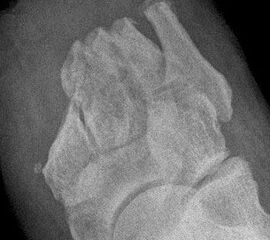

Der kraniale Calcaneus wird so mit der oszillierenden Säge reseziert, dass bei der Fusion mit der Tibia die physiologische Inklination von 30° wieder hergestellt wird (Abb. 48). Wird der Calcaneus zu steil eingestellt, kann das zu erhöhter Druckbelastung am Tuber calcanei und damit zur Ulzeration führen. Eine flache Einstellung des Talus wird von manchen Operateu­ren bevorzugt. Dies ist technisch vielleicht etwas einfacher, führt jedoch zu einer stärkeren Verkürzung. Varus- und Valgusfehlstellungen müssen vermieden werden.

Zur Osteosynthese bevorzugen wir 2-3 kanülierte Großfragmentschrauben (Abb. 49). Postoperativ ist die Extremität für 8 Wochen zu entlasten, wobei zur Sicherheit eine Entlas­tungsorthese verordnet werden kann. Bei schwachen oder unzuverlässigen Patienten empfiehlt es sich, für 8 Wochen einen Ring-Fixateur anzulegen.